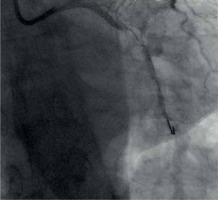

Dissection after predilatation, before BVS implantation, occurred in 22 patients, and in 17 of them it was covered by BVS implantation with optimal angiographic results. Five of them were finally in the dissection group. In another 4 patients from the dissection group, dissection appeared after BVS implantation and required additional intervention, but it was absent after predilatation. The description of dissection according to the NHLBI classification [2] is presented in Table I. Examples of angiographic images of individual dissection classes are shown in Table II.

Table II

Coronary artery dissection – classification